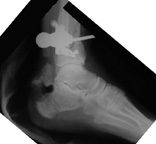

Tibia Fx ForumCase 1

I would appreciate treatment suggestions.My patient is a 30 year old with a very comminuted tibia fracture 6 weeks ago.It was grade 3B open. Initial treatment included irrigation, debridementClick images to enlarge.

and a hybrid external fixator including femur, tibia and foot. Screwswere placed in the plateau and plafond and a free flap plus STSG. Theskin is ok but atrophic. The femoral pins were removed and knee motionstarted at 6 weeks. There is no sign of callus. There is one pin inthe one large fragment of the diaphysis. All the pieces are lined upreasonably well. The XF pins are ok. Suggestions? Thank you.